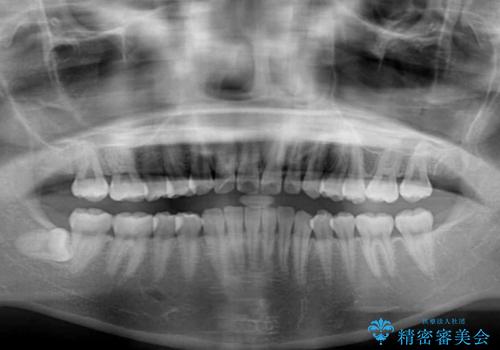

- 上の前歯の出っ歯を治したいとのことで来院された患者様です。

上下顎ともにIPR(歯と歯の間を削る)と歯列全体の拡大によって口元が引っ込むように設計し、インビザラインにより治療を行うこととしました。